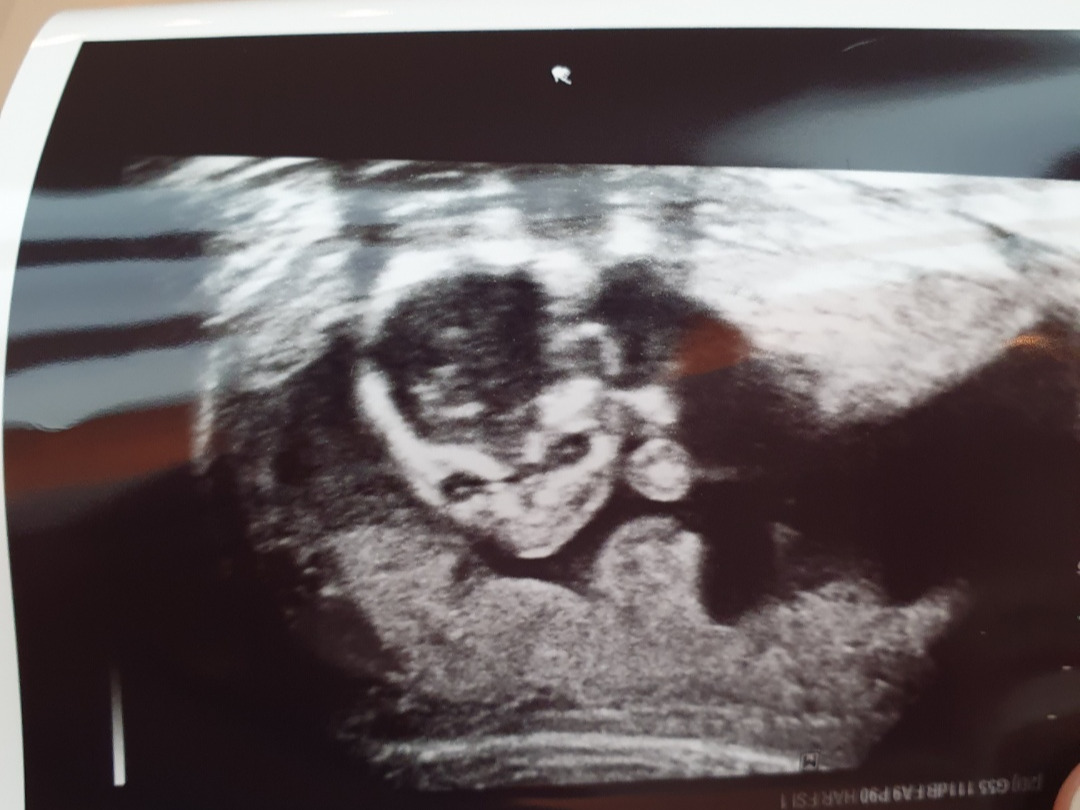

나의 주치의 선생님은 16주 검진 초음파에서 아이가 잘 자라고 있으며, 이제는 주수에 맞게 잘 크고 있는지 머리-엉덩길이 뿐만 아니라, 배둘레, 머리지름, 허벅지뼈길이 등을 재어 잘 크고 있다고 말씀하셨다. 기대하는 아기의 성별이 있냐고 묻길래, "다 좋아요!"라고 대답했는데, "다리 사이에 아무것도 없네요~"라고 넌지시 딸임을 알려주셨다. 딸이라니..! 써니는 여자아이였어!!!

벌써부터 도치맘 도치대디인 우리 부부는 딸바보가 될 준비를 검진이 끝나자마자 다 했다. 우리는 써니바보야.. 써니가 얼마나 예쁠까! 남편은 얼굴 윤곽이 얼핏 찍힌 초음파 사진을 보고 벌써부터 본인을 닮았다며 우겼다.

KakaoTalk_20220801_101346509.jpg 도대체 이 사진을 보고 어떻게 닮았다고 하는 건지는 모르겠지만...